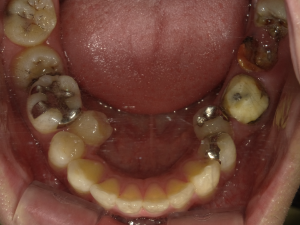

50代 女性 インプラント治療(GBR・ソケットリフト)

| 年代・性別 | 50代・女性 |

| 主訴 | Brの歯が取れそうなため、インプラントに変えたい。 |

| 部位 | 左下567 左上④5⑥ 右上67 |

| 治療期間 | 約3年9ヶ月 |

| 費用 | ¥3,224,500(税込) |

| 副作用・リスク |

|